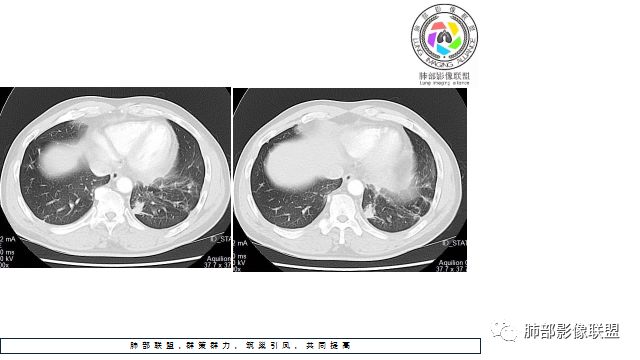

1.左下肺门区巨大肿块,支气管显示不清,轻度阻塞性炎症,没有明显肺不张,提示管腔受压狭窄可能性大于堵塞,这较少见于鳞癌。

2.病灶边缘光滑,未见明显分叶、毛刺,未见明显强化,这符合腺癌影像学特点,却符合神经内分泌癌表现。

3.病灶内密度均匀,轻到中度均匀强化,大病灶未见明显液化坏死区及空洞,不符合鳞癌而符合小细胞肺癌特点。

4.病灶内有肺动脉走形,血管局部受压,未见破坏,病灶乏血供,呈血管包埋或血管造影征;侵袭性力强及破坏力弱、血管漂浮都符合SCLC,所以鳞癌的可能性也不大。

5.左肺门块影或淋巴结肿大,竭力挤兑肺门血管结构,呈冰冻肺门;有时候SCLC可以单独呈现冰冻肺门,而没有没有冰冻纵隔。